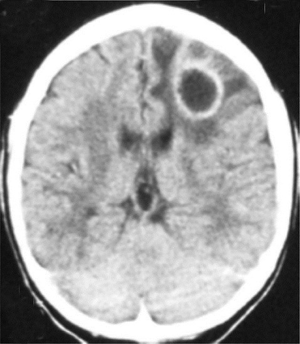

Ring-enhancing lesion

- CT or MRI with lesions having an enhancing ring of contrast around a less dense center can indicate certain neurological infections, injuries, and indolent disorders